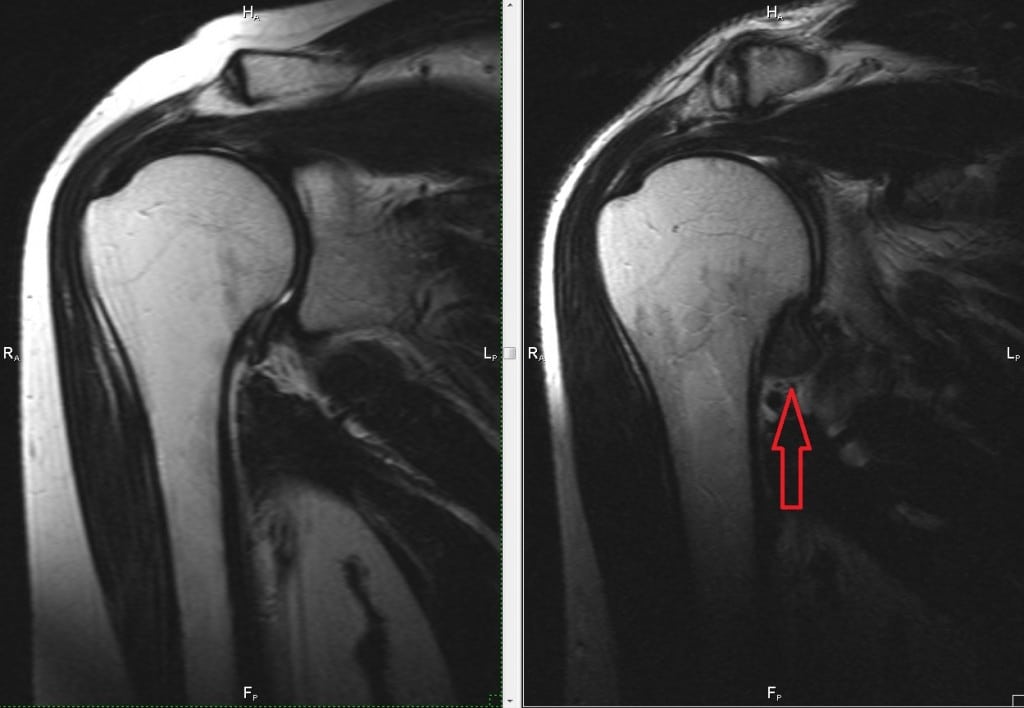

- магнитно-резонансная томография (МРТ). Более информативный диагностический метод. С его помощью можно обнаружить специфичное для болезни утолщение суставной капсулы. Однако из-за высокой стоимости МРТ практически не используют для диагностики капсулита;